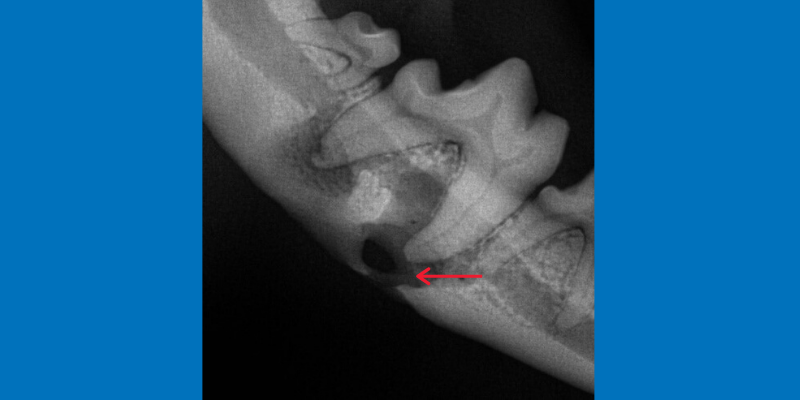

3. Missing Teeth and Tooth Roots

Missing teeth should always be x-rayed to be sure they aren’t hiding under the gumline. Teeth that have not erupted can lead to cysts and can be destructive to the jaw bones.

The first premolar appears to be missing on visual exam (left photo, white arrow), but on dental x-ray (right photo) is under the gumline and forming a cyst (red arrow).